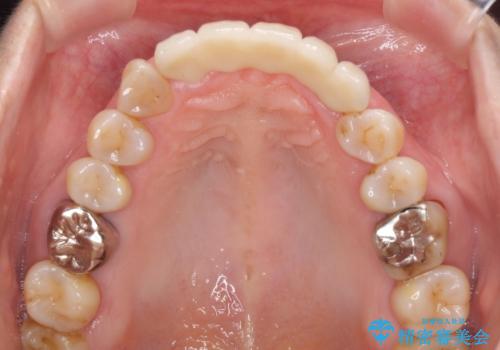

- アンバランスな色や形、歯肉ラインの黒い縁が目立ってしまったブリッジの作り直しを希望して来院された患者様です。

自然な仕上がりとするため、金属を使用しないオールセラミックブリッジにより補綴治療を行うこととしました。

装着されていたブリッジは、支台となっている歯と欠損している歯で色が大きく異なっていましたが、オールセラミックとしたことで、全体的に色調の整った仕上がりとなりました。

歯肉ラインがきれいに整い、患者様には大変満足していただきました。